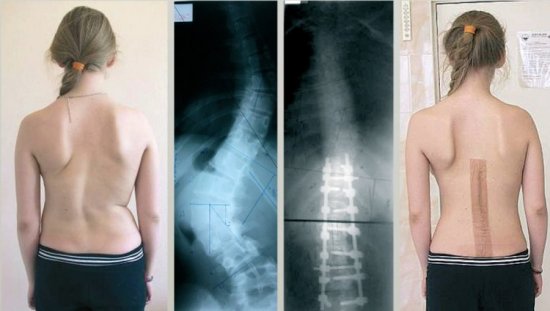

При запущенной стадии сколиоза врач прибегает к оперативному вмешательству. Чаще всего используется техника костно-пластического спондилодеза.

Что делать, если позвоночный столб искривлен более чем на 40 градусов? В этом случае может потребоваться хирургическая операция. Как правило, она применяется на четвертой стадии патологии в том случае, если прочие методы не дали нужного результата.

Проводить операцию должен врач-нейрохирург. Во время вмешательства в позвоночный столб устанавливается специальный стержень, оснащенный несколькими фиксаторами. Благодаря фиксаторам можно менять длину стержня по мере роста ребенка.

Обычно стержень остается в позвоночном столбе до момента окончания роста скелета, то есть до 24-25 лет. Однако иногда он не удаляется в силу того, что операция по его извлечению достаточно сложна и требует долгого реабилитационного периода.